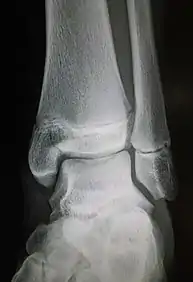

| Radiograph showing a Maisonneuve fracture of the proximal fibula | |

Ankle radiographs are used to detect widening of the tibiofibular syndesmosis or medial clear space. The medial clear space is the area between the talus of the ankle and the medial malleolus. Damage to the deltoid ligament and syndesmotic ligaments result in mortise instability, causing the talus to laterally shift and widen the medial clear space.[4][12] A clinical study, conducted in 2006 and published in the Journal of Bone and Joint Surgery, found that the medial clear space size of a normal ankle and an injured ankle measured at 4 millimetres and 5.4 millimetres in length respectively.[11] To confirm diagnosis, full-leg radiographs are used to inspect for fractures of the proximal fibula and widening of the interosseous clear space (or tibiofibular clear space). The interosseous clear space is the area between the medial side of the fibula and lateral side of the tibia. A peer-reviewed study, published in Injury in 2004, found that an interosseous clear space greater than 10 millimetres indicates diastasis of the syndesmotic ligaments.[4]

If necessary, Computed Tomography (CT) or Magnetic Resonance Imaging (MRI) may also be used to clarify diagnosis. MRI scans can check for interosseous membrane or tibial tubercle damage if high instability of the ankle is diagnosed.[8][11] Arthroscopy may be used to diagnose a syndesmotic lesion but is often not recommended due to operative difficulty.[13] Stress radiographs of the ankle are used to assess the integrity of the deltoid ligament and tibiofibular syndesmosis.[9][13] The size of the medial clear space can also be measured using stress radiography.[11]

X-ray, CT, or MRI scans can be used to diagnose the extent of the Maisonneuve fracture's damage and determine whether it is a simple or comminution fracture.[8] During diagnosis, a supination-external rotation pattern of injury may also be concluded if there is an isolated fracture of the posterior tubercle of the tibia.[9]